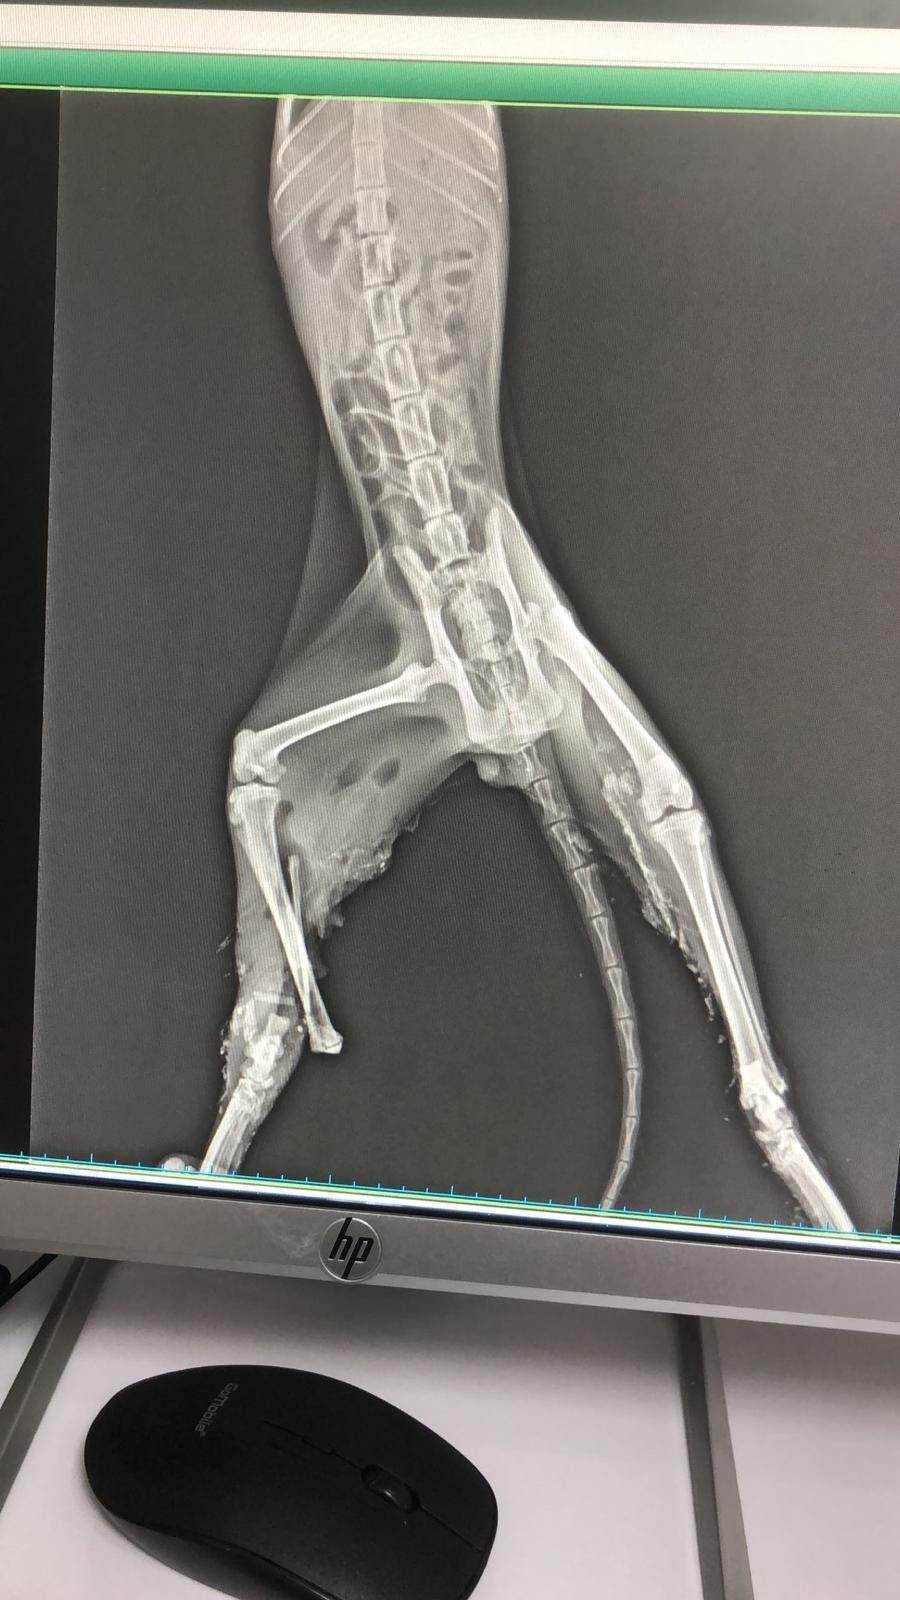

Gipsy was found dragging herself through the streets — in pain, scared, and completely helpless. A kind stranger rushed her to the local shelter, hoping she’d finally get the care she so desperately needed. But days passed, and nothing changed. The shelter admitted they didn’t have the resources to perform the surgery she urgently needs.

Now, Gipsy is fighting two heartbreaking battles:

A painful fracture that makes every step agonizing

A severe infection that threatens her life

Veterinarians have made it clear: Gipsy needs surgery within days, and immediate treatment is needed to stop the infection from spreading. Time is running out — but her story doesn’t have to end this way.